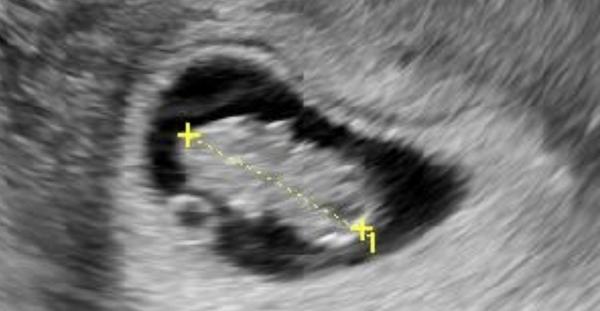

@jajajungmannova aha tak to nevím. Posílám pro představu jak vypadalo naše mimi v 8tt. Ta malá kulička je zloudkovy vak a velké mimco